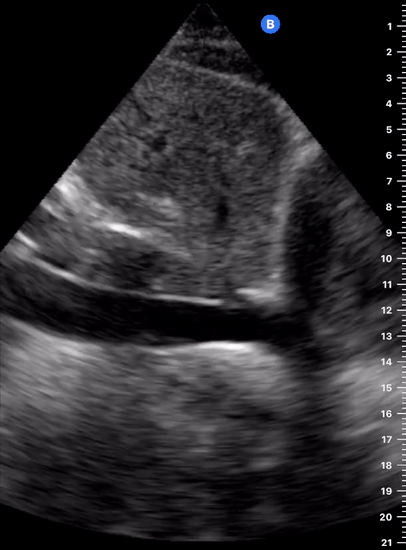

The IVC diameter changes depending on intravascular volume status, and normally, the IVC collapses during spontaneous inspiration. Therefore, the IVC diameter represents a non-invasive method for estimating central venous pressure (CVP). The evidence suggests that in spontaneously breathing patients, there is a good correlation between the sonographic estimation of CVP and values measured with invasive methods (2). IVC filling and CVP, however, allow only a rough correlation with volume status, and the sonographic estimation of preload should at least include the assessment of the LV and the Lung. Thus, it is better to think of IVC filling as an indicator of fluid tolerance, instead of a determinant of fluid responsiveness (6).

IVC exploration is best from the subxiphoid approach with longitudinal and transverse images. The IVC should be assessed in terms of overall size and collapsibility. The diameter is typically measured at its largest (end of expiration) at 1-2 cm distal to where the hepatic veins join the vena cava. An IVC diameter of ≥ 2 cm, especially with minimal or no collapsibility, is considered plethoric and correlates with increased RA pressure. An IVC of < 1 cm, particularly with complete collapse, is considered flat and indicates low preload and potential fluid responsiveness. An IVC diameter between 1 and 2 cm is typically normal.

PITFALLS

In a long-axis view, beware of not sliding off the centre of the vessel, as this will underestimate the size of the IVC and overestimate its collapse. Obtaining long and short axis views may help avoid this pitfall. Another mistake is confusing the descending aorta for the IVC, particularly when scanning in long-axis. Although the IVC may appear to pulsate, the aorta has a thicker wall, and its position is to the patient’s left. Following the IVC upwards will reveal the hepatic veins junction and the entrance to the RA, while the aorta will travel behind the heart. The IVC moves both anterolaterally and craniocaudally with inspiration, and this should be considered during visualization or measuring. For this very reason, measuring in M-mode is not recommended as it would not be accurate.

SHOCK

In a shocked patient, a flat or highly collapsible IVC correlates well with low preload estates (hypovolaemia, haemorrhage, sepsis). Yet by itself, a small IVC is not enough to define low preload and could also represent a normal finding.

Conversely, a distended, not collapsing IVC suggests distal obstruction in a shocked patient. Potential causes include LV failure, massive PE, tension pneumothorax and cardiac tamponade. Nonetheless, there are other causes of elevated cava / RA pressure, such as chronic pulmonary hypertension.